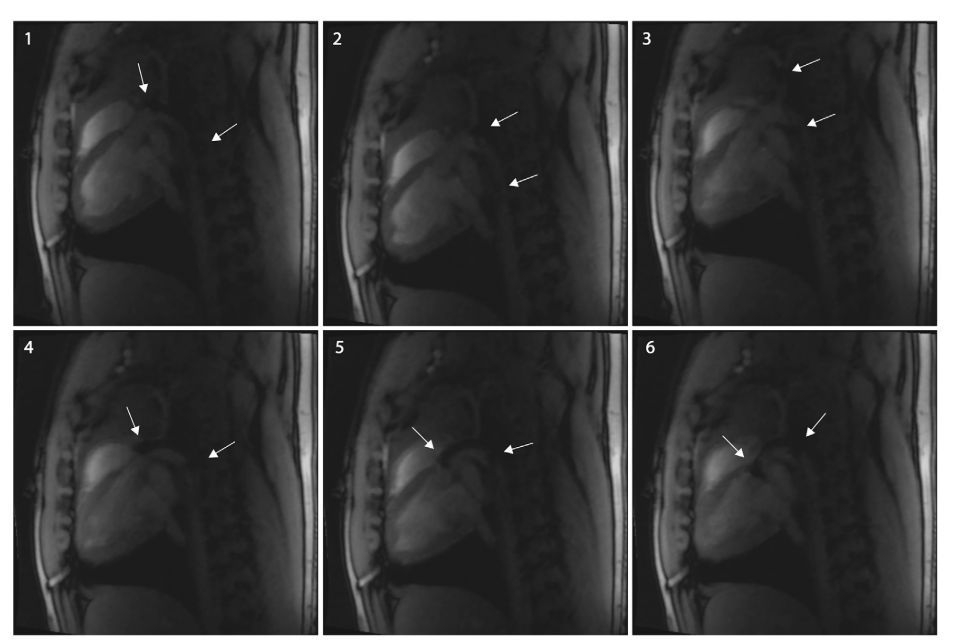

图5. MRI 序列图,1 为导管向主动脉弓推进,2-3 为导管指向颈动脉,4-5 为导管转向主动脉弓,6 为导管穿过主动脉弓到达主动脉根部,箭头标注导管尖端标记)

该图(图5)以时序 MRI 影像,完整记录了 steerable 导管在猪体内从外周血管到主动脉根部的导航过程,直观展示了其在复杂解剖结构中的通过性和操控性。